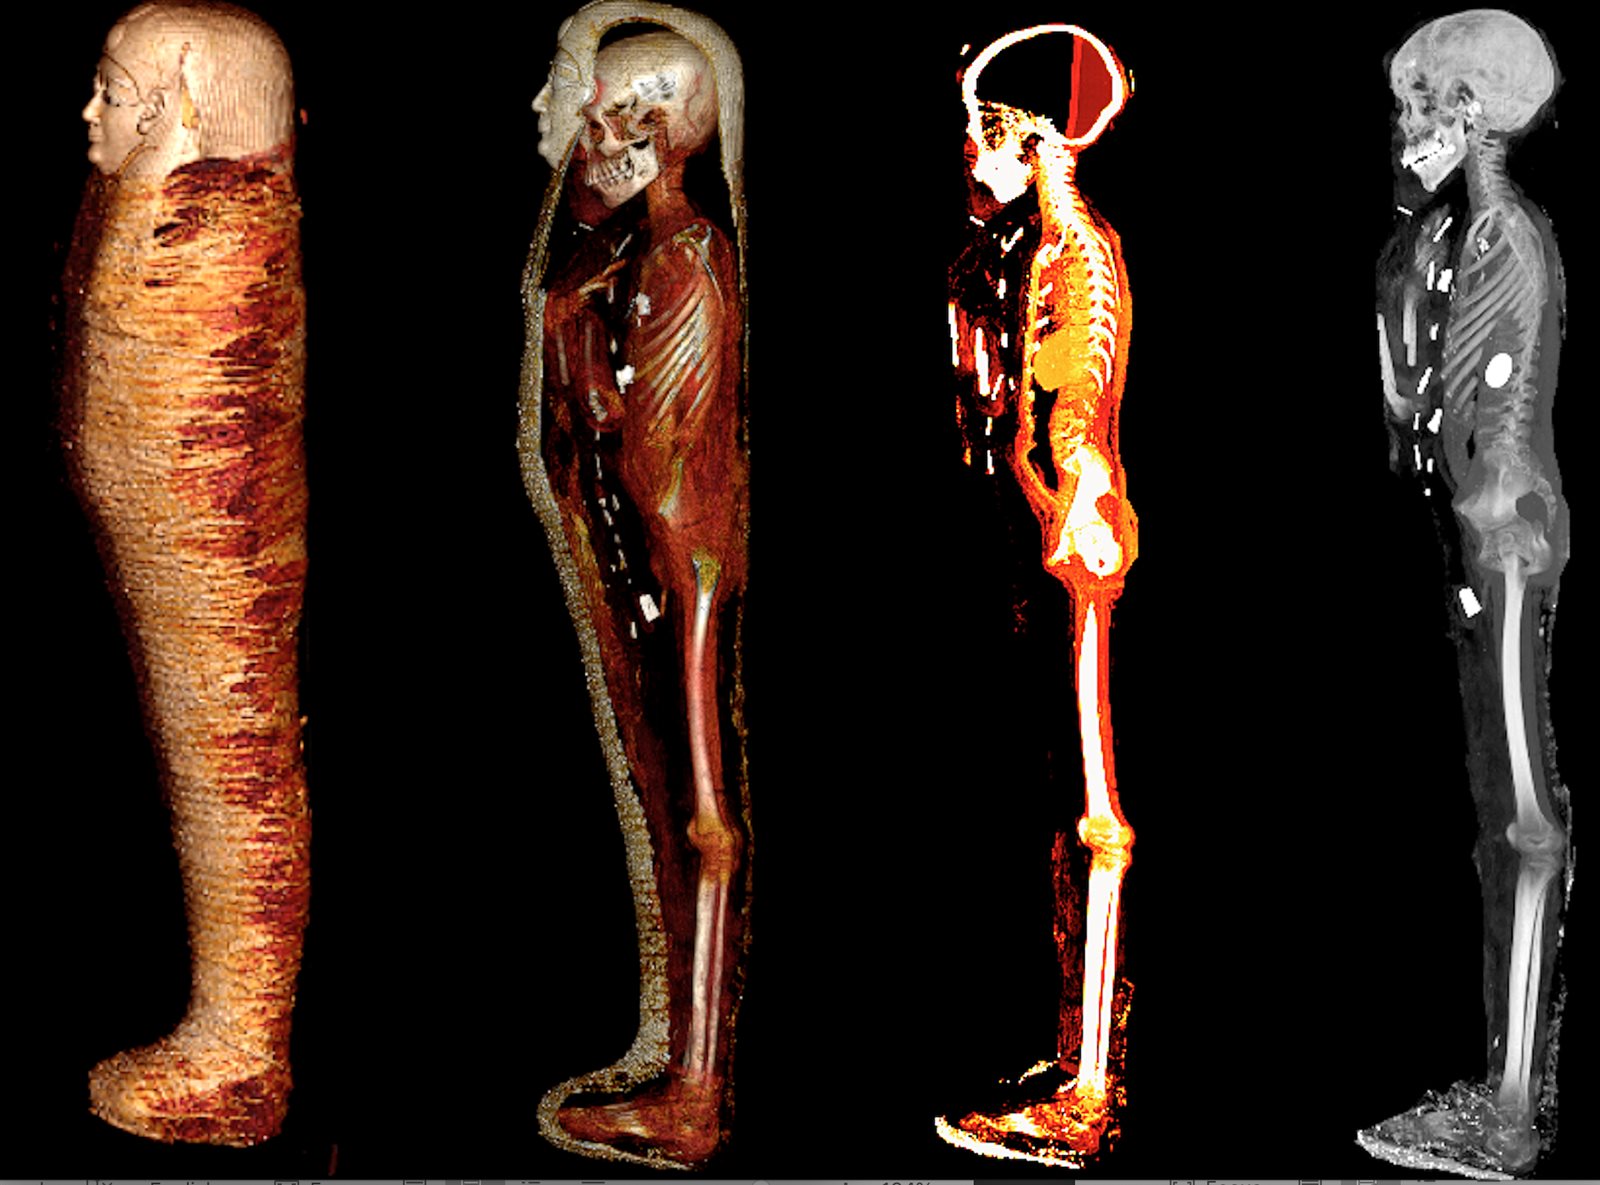

كشفت الأشعة المقطعية والطباعة ثلاثية الأبعاد أسرار مومياء الصبي الذهبي المخزنة في بدروم المتحف المصري بالتحرير لأكثر من قرن من الزمان، وتم نشر نتائج هذه الدراسات العلمية بمجلة Frontiers in Medicine اليوم 24 يناير 2023، والتي أسفرت عن الكشف عن هوية هذه المومياء وحالة حفظها وما تحتويه من أسرار.

تم العثور على هذه المومياء ملفوفة بالكامل بالكتان عام 1916، داخل مقبرة من العصر البطلمي (حوالي 300 ق.م.) بمدينة إدفو بمحافظة أسوان حيث تم نقلها وحفظها، آنذاك، ببدروم المتحف المصري بالتحرير دون فحص لأكثر من قرن من الزمان، حتي تم فحصها لأول مرة عام 2015 من قبل الدكتورة سحر سليم أستاذ الأشعة بكلية الطب جامعة القاهرة، بالتعاون مع صباح عبد الرازق مدير عام المتحف المصري بالتحرير، ومحمود الحلوجي المدير الأسبق للمتحف، باستخدام الأشعة المقطعية، بشكل آمن، من خلال الجهاز الموجود بالمتحف واستخدام الأشعة المتقدمة وبرامج الكمبيوتر الحديثة وكذلك الطباعة ثلاثية الأبعاد.

وأوضحت الدكتورة سحر سليم أن المومياء لصبي توفي عن عمر يناهز 15 عاما وأنه تم تحنيطها باتقان كبير، وتم إزالة المخ من خلال فتحة الأنف ووضع الحشوات والراتنج داخل تجويف الجمجمة. كما تم إزالة الأحشاء من خلال شق صغير أسفل البطن ووضع الحشوات والراتنج بداخل الجسم، بينما حرص المحنطون علي الإبقاء علي القلب الذي تم رؤيته في صور الأشعة بداخل تجويف الصدر.

وأضافت الدكتورة سحر سليم إلى أن الأشعة أوضحت ما بداخل اللفائف حيث ترتدي المومياء قناعًا ذهبيًا وصدرية مصنوعة من الكارتوناج وصندلًا من النسيج.

وأكدت الدكتورة سحر سليم أن الدراسة كشفت عن وجه المومياء لأول مرة بعد إزالة اللفائف بشكل افتراضي بتقنية الأشعة المقطعية، حيث أتاحت الدراسة فرصة فريدة لاكتشاف أسرار تحنيط المومياء دون المساس باللفائف، وكما تركها المصريين القدماء.